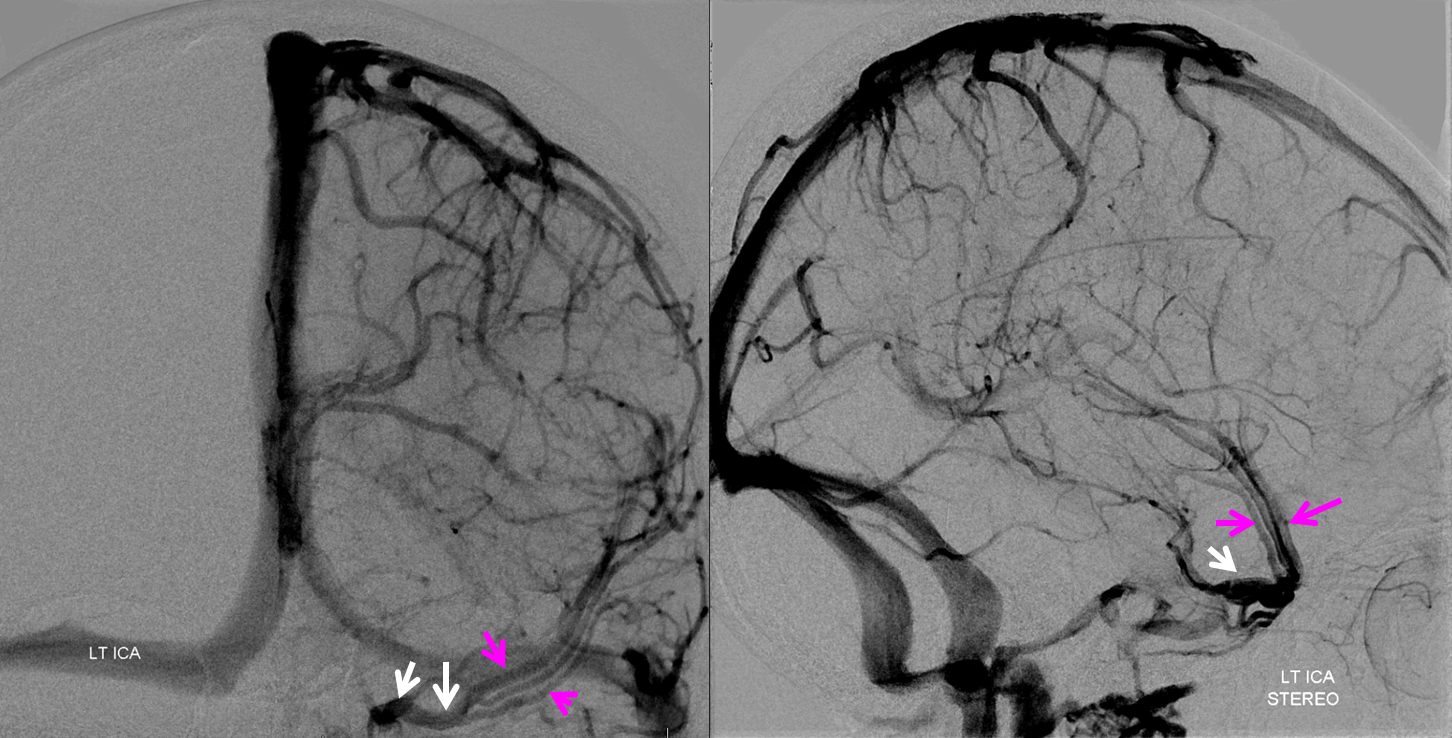

Below is an example of as large an inferior sagittal sinus (white) as one is likely to ever see under non-pathologic circumstances. Why is this sinus so large? Again, the answer is that veins are like rivers — the inferior sagittal sinus happens to be receiving a completely benign, nonpathologic mesial anterior frontal vein (blue arrows). However, the increased inflow into the Galen system has likely resulted in alternate drainage of the basal vein (purple) into the superior petrosal sinus via the lateral mesencephalic vein (black) — see deep venous system and veins of posterior fossa pages for more info. Also notice a large emissary vein (pink)

Stereo of the same